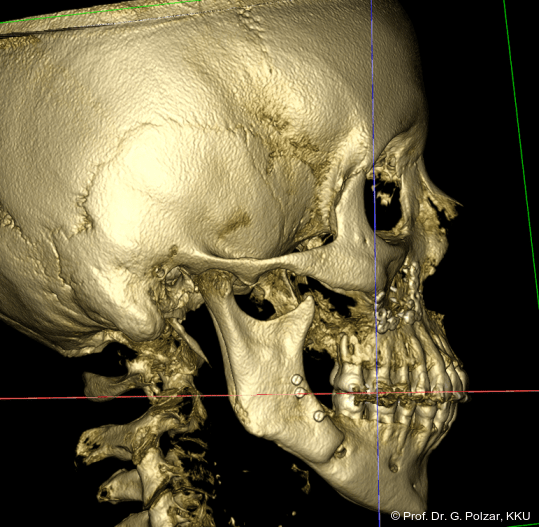

KG-Position: Die 3D-Ansicht im DVT zeigt eine vorverlagerte UK-Position bei neutraler Okklusion (Abb. 4a+b).

Im Sagittalschnitt zeigen beide Kiefergelenke eine deutlich anteriore Position. Der dorsokraniale Abstand betrug rechts 7,0 mm und links 5,8 mm. In der PEP waren sie im lateralen Bereich ca. 1 mm kleiner als in der Mitte der Sagittalprojektion (Abb. 6a–d).

Diese deutlich anteriore Gelenkposition im Neutralbiss ließ den Verdacht auf einen Sunday Bite zu. Das heißt, die Patientin schob den Unterkiefer aktiv nach vorne, um damit schönere Schneidezahnkontakte bzw. eine vermeintlich neutrale Okklusion zu erreichen. Nach mühsamen Lockerungsübungen gelang es der Patientin, auch in die zen­trale Kiefergelenkposition zu wechseln. So zeigte sich das ganze Ausmaß der Malokklusion. In neutraler KG-Position hatte die Patientin eine sagittale Frontzahnstufe von ca. 7 mm mit 1 PB Klasse II-Okklusion im Seitenzahn­bereich (Abb.5a+b, 7a–c).